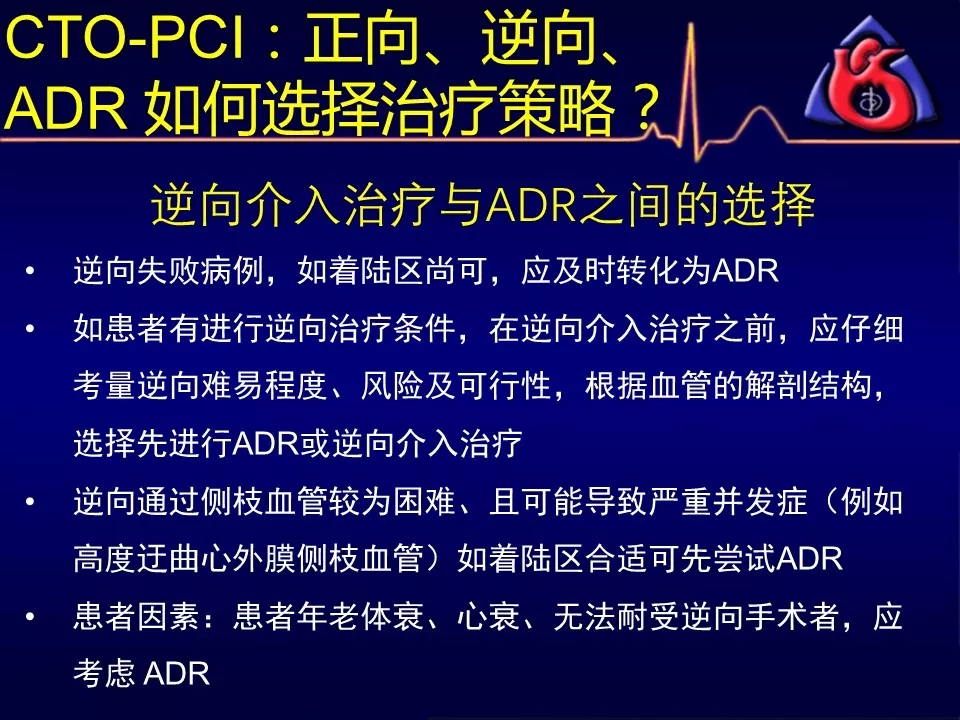

如何选择正向、逆向、IVUS指引及ADR技术?

既往逆向技术尝试失败,再次逆向成功率不高者

当逆向技术困难时,如解剖条件许可,应优选ADR

逆向技术无条件(无可利用侧枝血管)